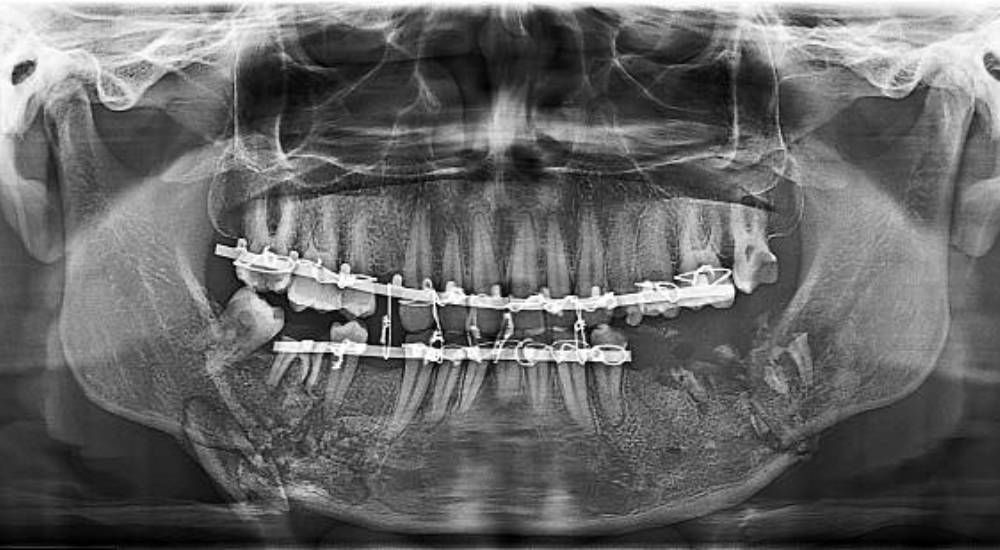

Complete Orthodontic Studies – $60

For patients beginning orthodontic treatment, we conduct complete diagnostic studies including panoramic X-rays, cephalometric radiographs, digital photos, and detailed impressions or digital scans. These records allow us to create precise treatment plans and track your progress throughout treatment. This comprehensive analysis ensures optimal results and efficient treatment timing.